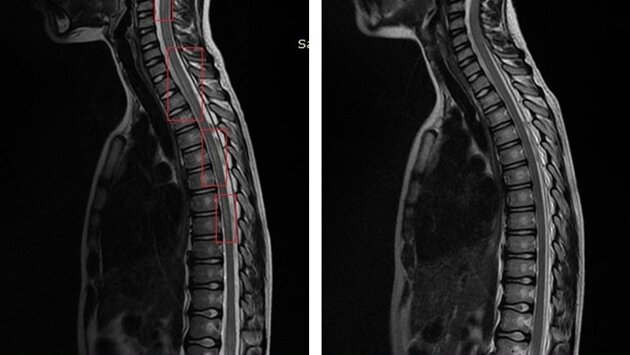

Все показатели, которые могли бы указывать на заболевания почек, были в норме, пациент был проконсультирован нефрологом. Мы заподозрили патологию спинного мозга, в том числе и миелит, то есть воспалительное поражение. Удалось оперативно провести все необходимые исследования, в том числе и МРТ, и своевременно поставить диагноз. Спинной мозг был полностью просмотрен, поставлен диагноз – острый миелит, – рассказала врач-невролог детской областной больницы Ирина Крутихина.